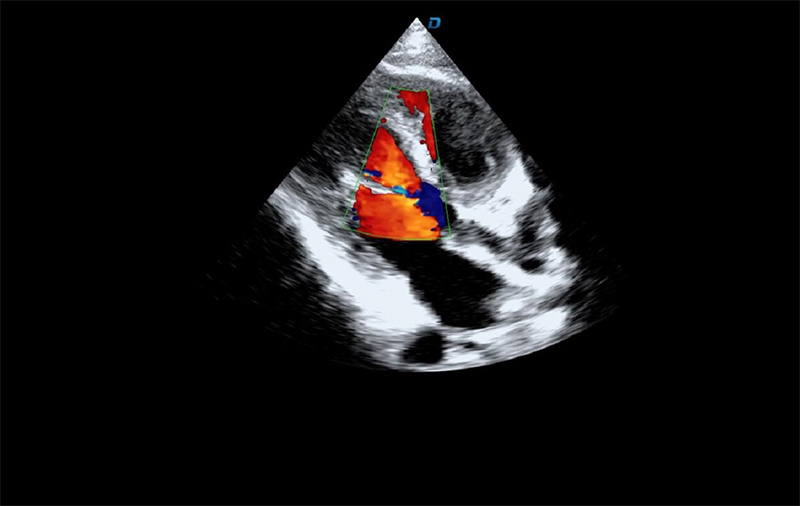

心臟彩超機(jī)檢查

有些心臟病會(huì)引起心臟電活動(dòng)的改變,但是有些心臟的疾病卻不影響心電,而只影響心臟本身的結(jié)構(gòu)。比如心臟擴(kuò)大,心臟收縮無(wú)力,心臟的瓣膜關(guān)閉不嚴(yán)密,這些疾病的診斷及發(fā)現(xiàn)更多的依賴(lài)于心臟彩超,這些病變一般不隨癥狀的緩解而緩解。心臟超聲心動(dòng)圖,不需要開(kāi)胸,就可以看到心臟的大小、內(nèi)部結(jié)構(gòu)、瓣膜運(yùn)動(dòng)情況等。除了探頭壓迫可能會(huì)有疼痛或不適感外,對(duì)患者沒(méi)有任何創(chuàng)傷。

臨床上,心臟超聲心動(dòng)圖主要用于對(duì)各種先心病、心臟瓣膜病的診斷;各種心肌病、心包疾病的診斷和心臟功能的評(píng)估。部分嚴(yán)重肺氣腫、胸廓畸形等患者,因?yàn)槌晥D像質(zhì)量欠佳而診斷效果受到一定限制。